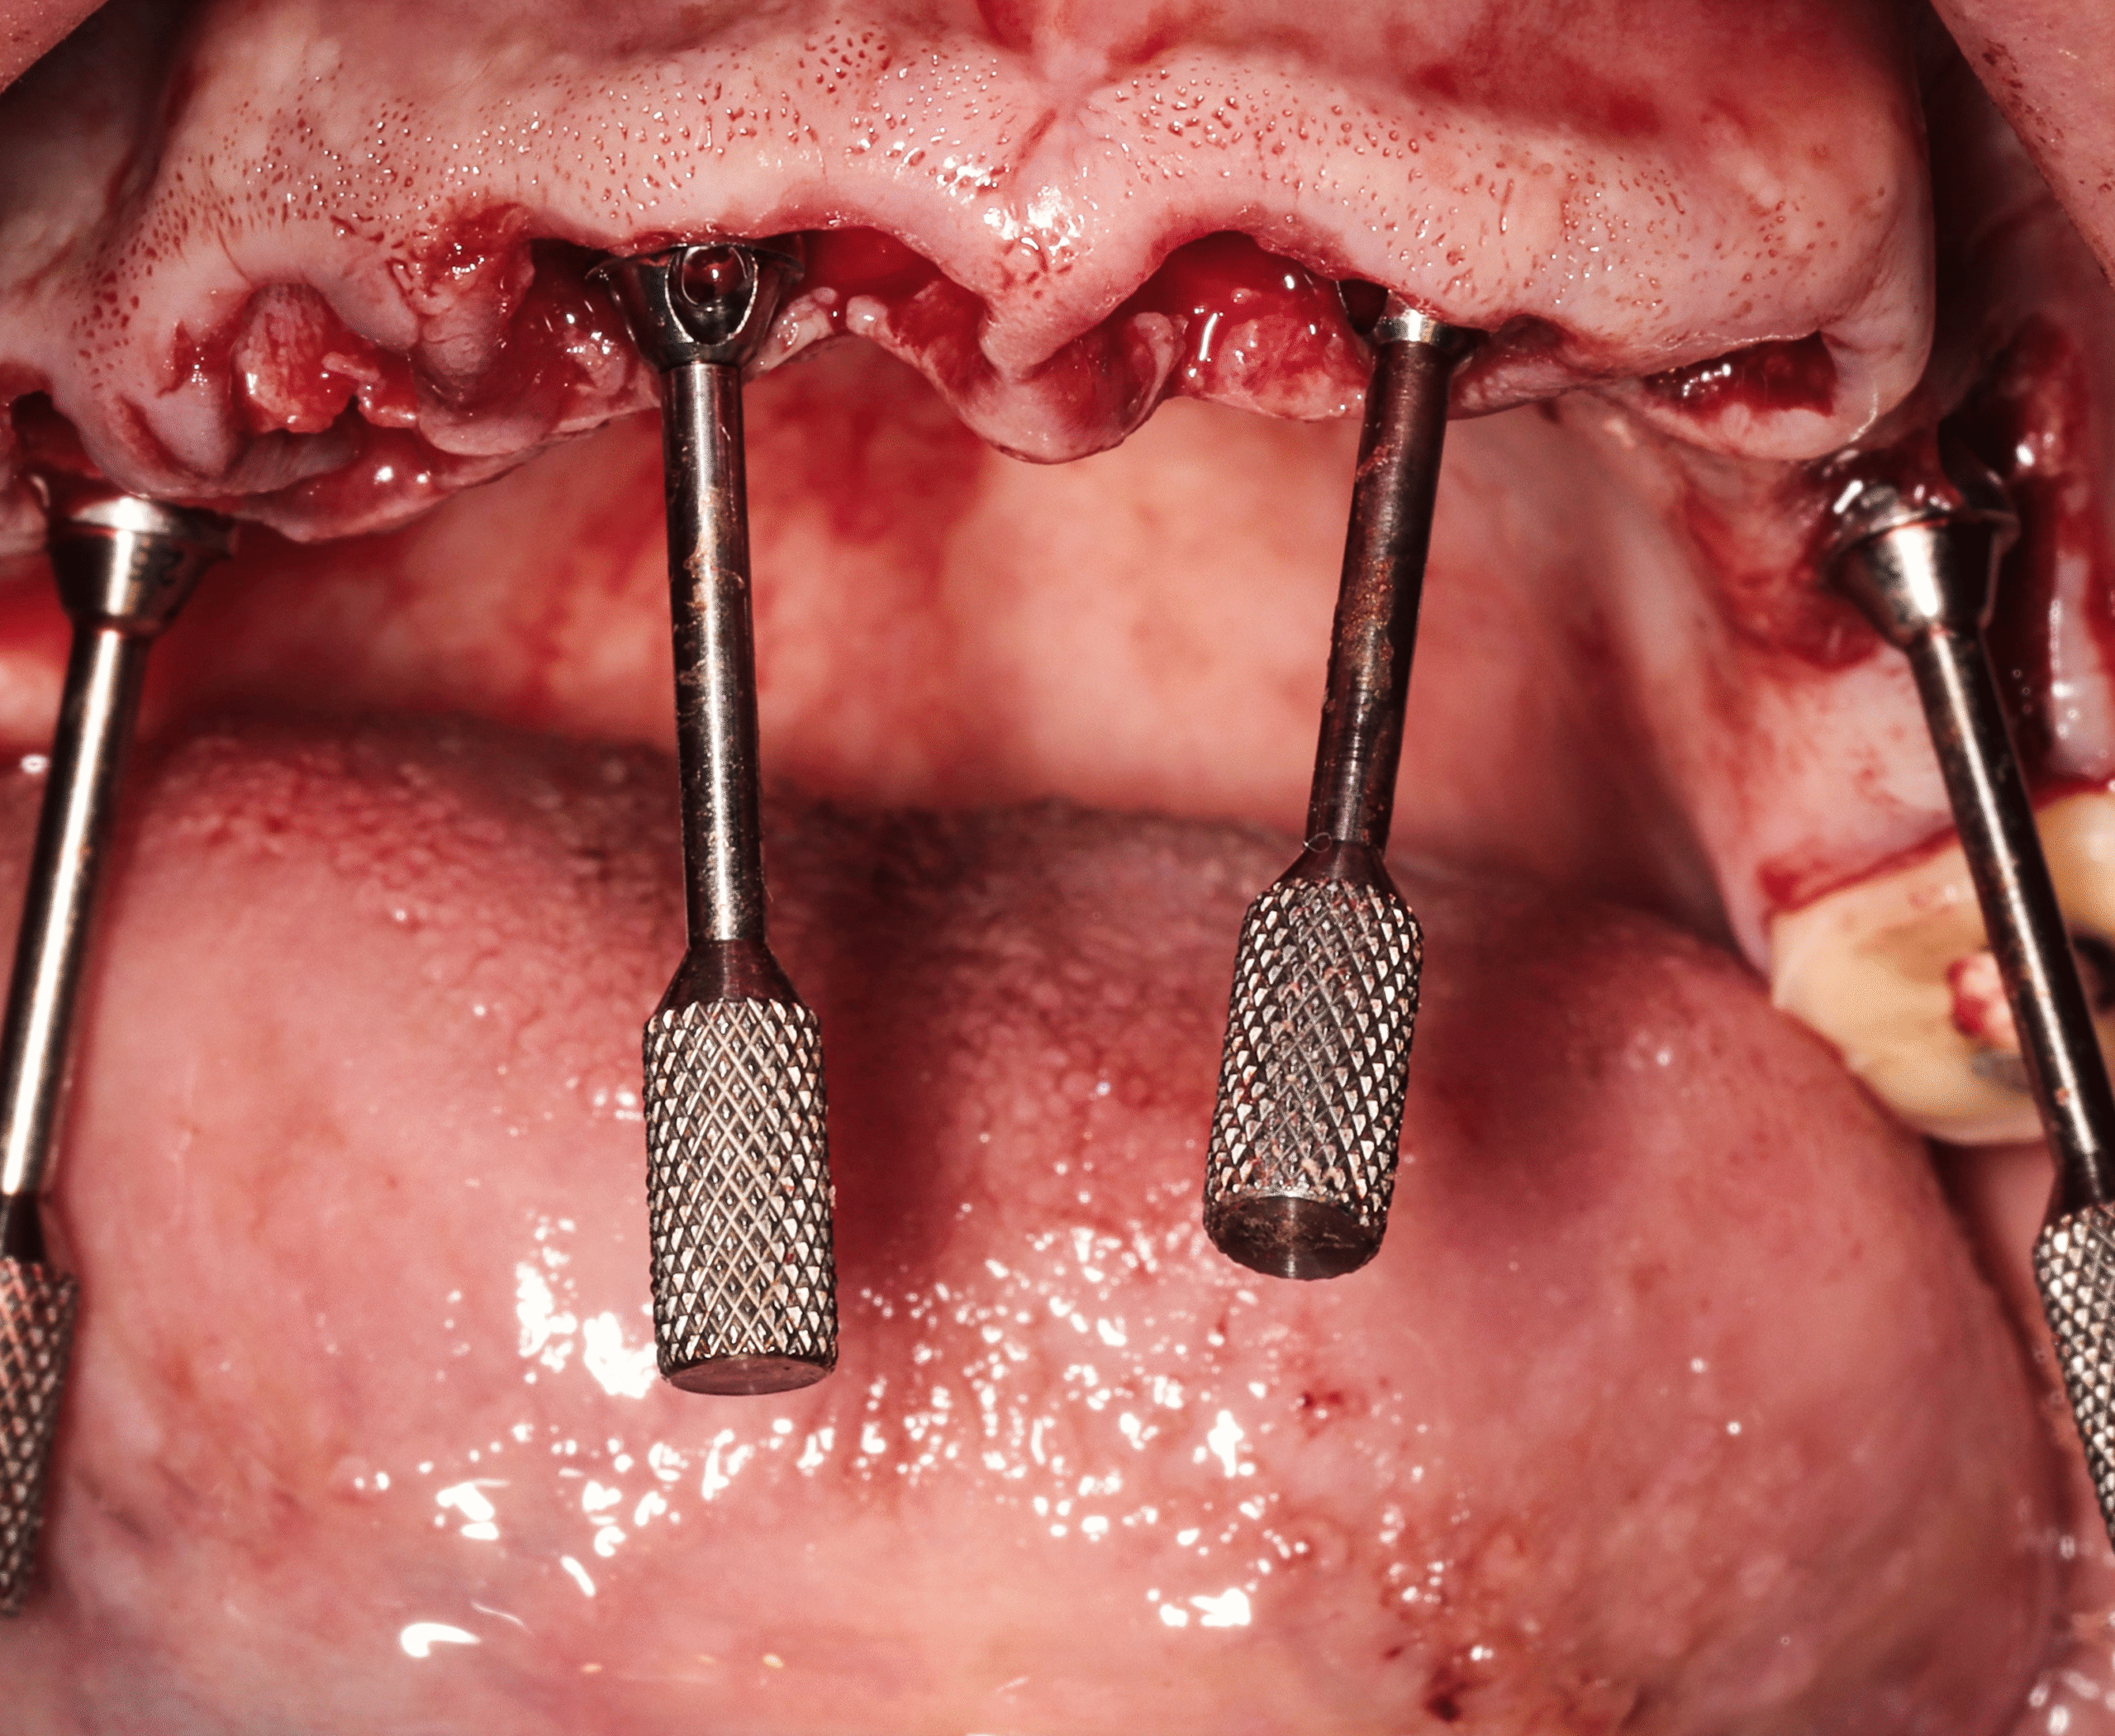

Step 3 — Strategic Implant Placement (All-on-Four)

- Placement of four implants in each arch

- Angled posterior implants used to maximize available bone without grafting

- Achieved strong primary stability suitable for immediate loading